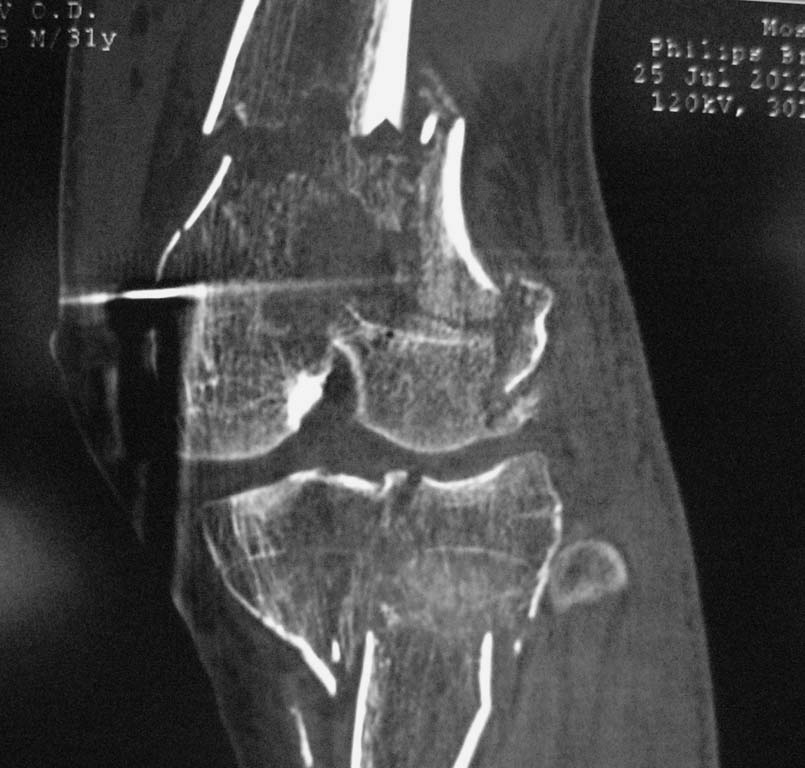

Нужен совет. Открытый перелом в\3 диафиза с оскольчатым переломом дистального метаэпифиза бедра. Закрытый оскольчатый внутрисуставной перелом проксимального отдела большеберцовой кости той же конечности.При поступлении ПХО ран, скелетное вытяжение. Рана зажила первичным натяжением. Осложнилось правосторонней пневмонией. Предстоит выбрать тактику оперативного лечения и камими имплатнатами.По нашему мнению случай нестандартный, требуется обсуждение коллег.

Добрый вечер. На проксимальное бедро длинную гамму. Внутрисуставные переломы только открыто. На бедренную кость опорную мыщелковую пластину LCP. На голень две Г образные LCP с латеральной и медиальной стороны. Возможна менискэктомия. Активные движения в коленном суставе в раннем п/о периоде. Оперировать желательно на ортопедической приставке.

Спасибо большое за совет, мы выбрали именно эту тактику. Диафиз бедра, учитывая то, что линия перелома идет до малого вертела, зафиксировали длинной PFNA, мыщелки бедра собирали на LISS. Вторым этапом большеберцовую кость проксимальной латеральной пластиной, правда только одной. Голень получилась не идеально, имеется варусный угол. Все имплантаты Synthes. Снимки с iPAD не получается скинуть. Если не заленюсь, дома скину с компа.